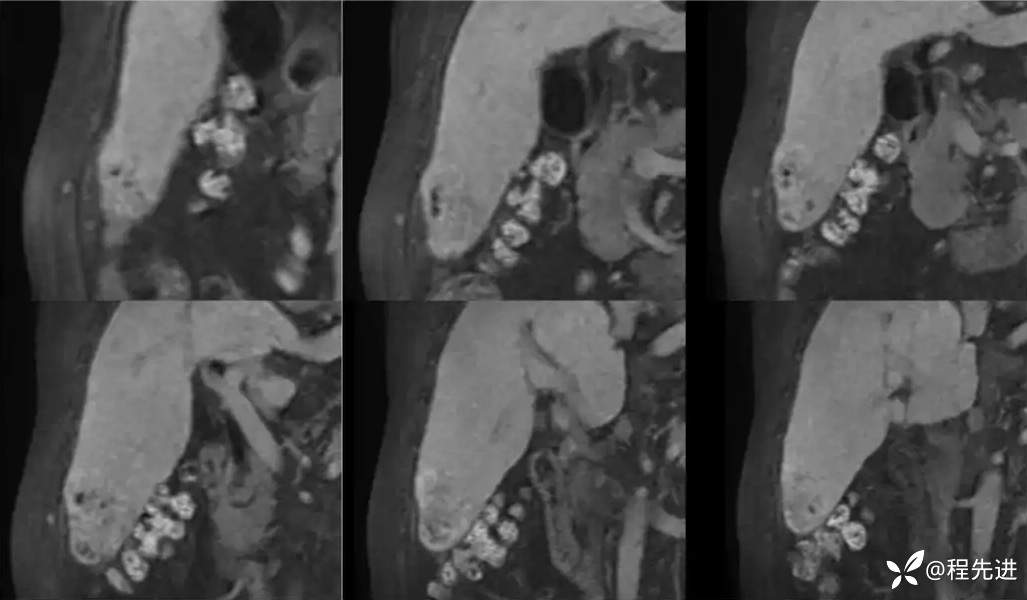

移行期冠状位:

肝胆期: